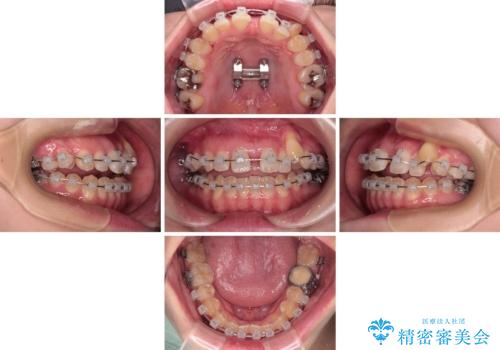

急速拡大装置 狭い上顎骨を拡大してワイヤー装置で八重歯を短期間治療

- 上顎の八重歯やデコボコを気にして来院された患者様です。

上顎歯列が狭窄していたため、急速拡大装置により上顎骨を側方に拡大しながら、ワイヤー装置にて矯正治療を行うこととしました。

上顎骨を拡大することで、八重歯やデコボコを歯列に収めることができ、下顎の歯が外に位置していた奥歯の咬み合わせも改善することができました。

スペースも短期間に獲得できるため、1年程度で治療を終えることができました。